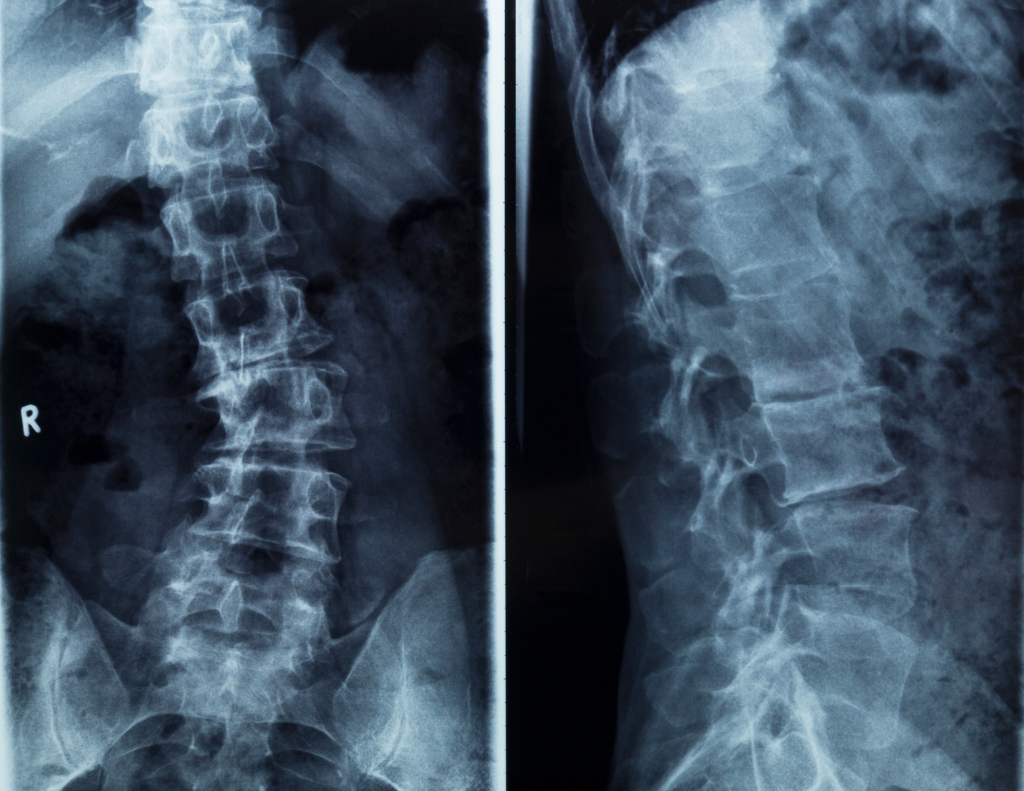

Scoliosis: Everything you need to know and 10 FAQs answered

Does your spine have more curves than a mountain highway? You’re definitely not alone. Scoliosis affects approximately 2-3% of the global population, with an estimated 6-9 million people living with this condition in the United States alone. At Enhanced Physio’s Runcorn and Southport clinics, we see patients with scoliosis regularly, and here’s the encouraging news: […]

Ankylosing Spondylitis: Let’s Untwist This Spine!

Hey there, health enthusiasts! Today, we’re diving into a topic that may sound like a mouthful but is really quite important: ankylosing spondylitis (AS). This inflammatory disease may not be on everyone’s radar, but understanding it can help you keep your spine flexible and your posture upright. Let’s get started—spine straight, coffee in hand! What […]